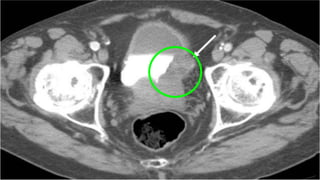

IMAGING STUDIES….. EAU

INTRAVENOUS UROGRAPHY …..

ADVANTAGES

Intravenous urography (IVU) can be an

alternative if CT is not available.

In muscle-invasive tumours of the bladder and in

Upper Tract Urothelial Carcinomas, CT Urography

gives more information than IVU (including status

of lymph nodes and neighbouring organs).

IMAGING STUDIES….. EAU INTRAVENOUSUROGRAPHY ….. ADVANTAGES Intravenous urography (IVU) can be an alternative if CT is not available. In muscle-invasive tumours of the bladder and in Upper Tract Urothelial Carcinomas, CT Urography gives more information than IVU (including status of lymph nodes and neighbouring organs).